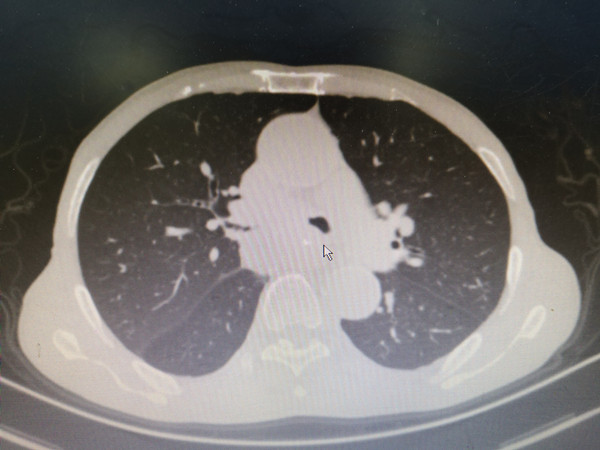

据悉,该患者为晚期食道癌并大气道转移,极度呼吸困难。从今年8月份开始,先后辗转西安2家三甲医院,因气道内病变复杂,未给予气道内治疗致气道阻塞逐渐加重,患者呼吸也来越困难困难。2021年12月17日,由当地医院转入二附院呼吸与危重症医学科。入院时患者端坐呼吸,不能平卧,说话不能成句,呼吸困难严重。气道三维重建显示左侧气道90%狭窄,右侧气道几乎完全堵塞。需紧急打通气道,挽救患者生命。

鉴于我院严峻的疫情防控形势下,麻醉科在工作人员非常紧缺的情况下紧急协调,12月21日11点,在麻醉科李卫松、郑思敏医生协助下,我科张德信副教授急诊为患者行硬支气管镜下气道再通术。手术首先采用激光打通阻塞相对较轻的左侧支气管,保证通气后,再采用激光打通右侧气道,暴露右肺上叶,后经球囊扩张右肺下叶,可见较多量痰液涌出,提示右肺下叶也恢复通气,提示手术成功完成。随后为患者定制Y型支架置入,维持较久疗效。手术历经2个多小时。患者清醒后自觉呼吸困难完全缓解。